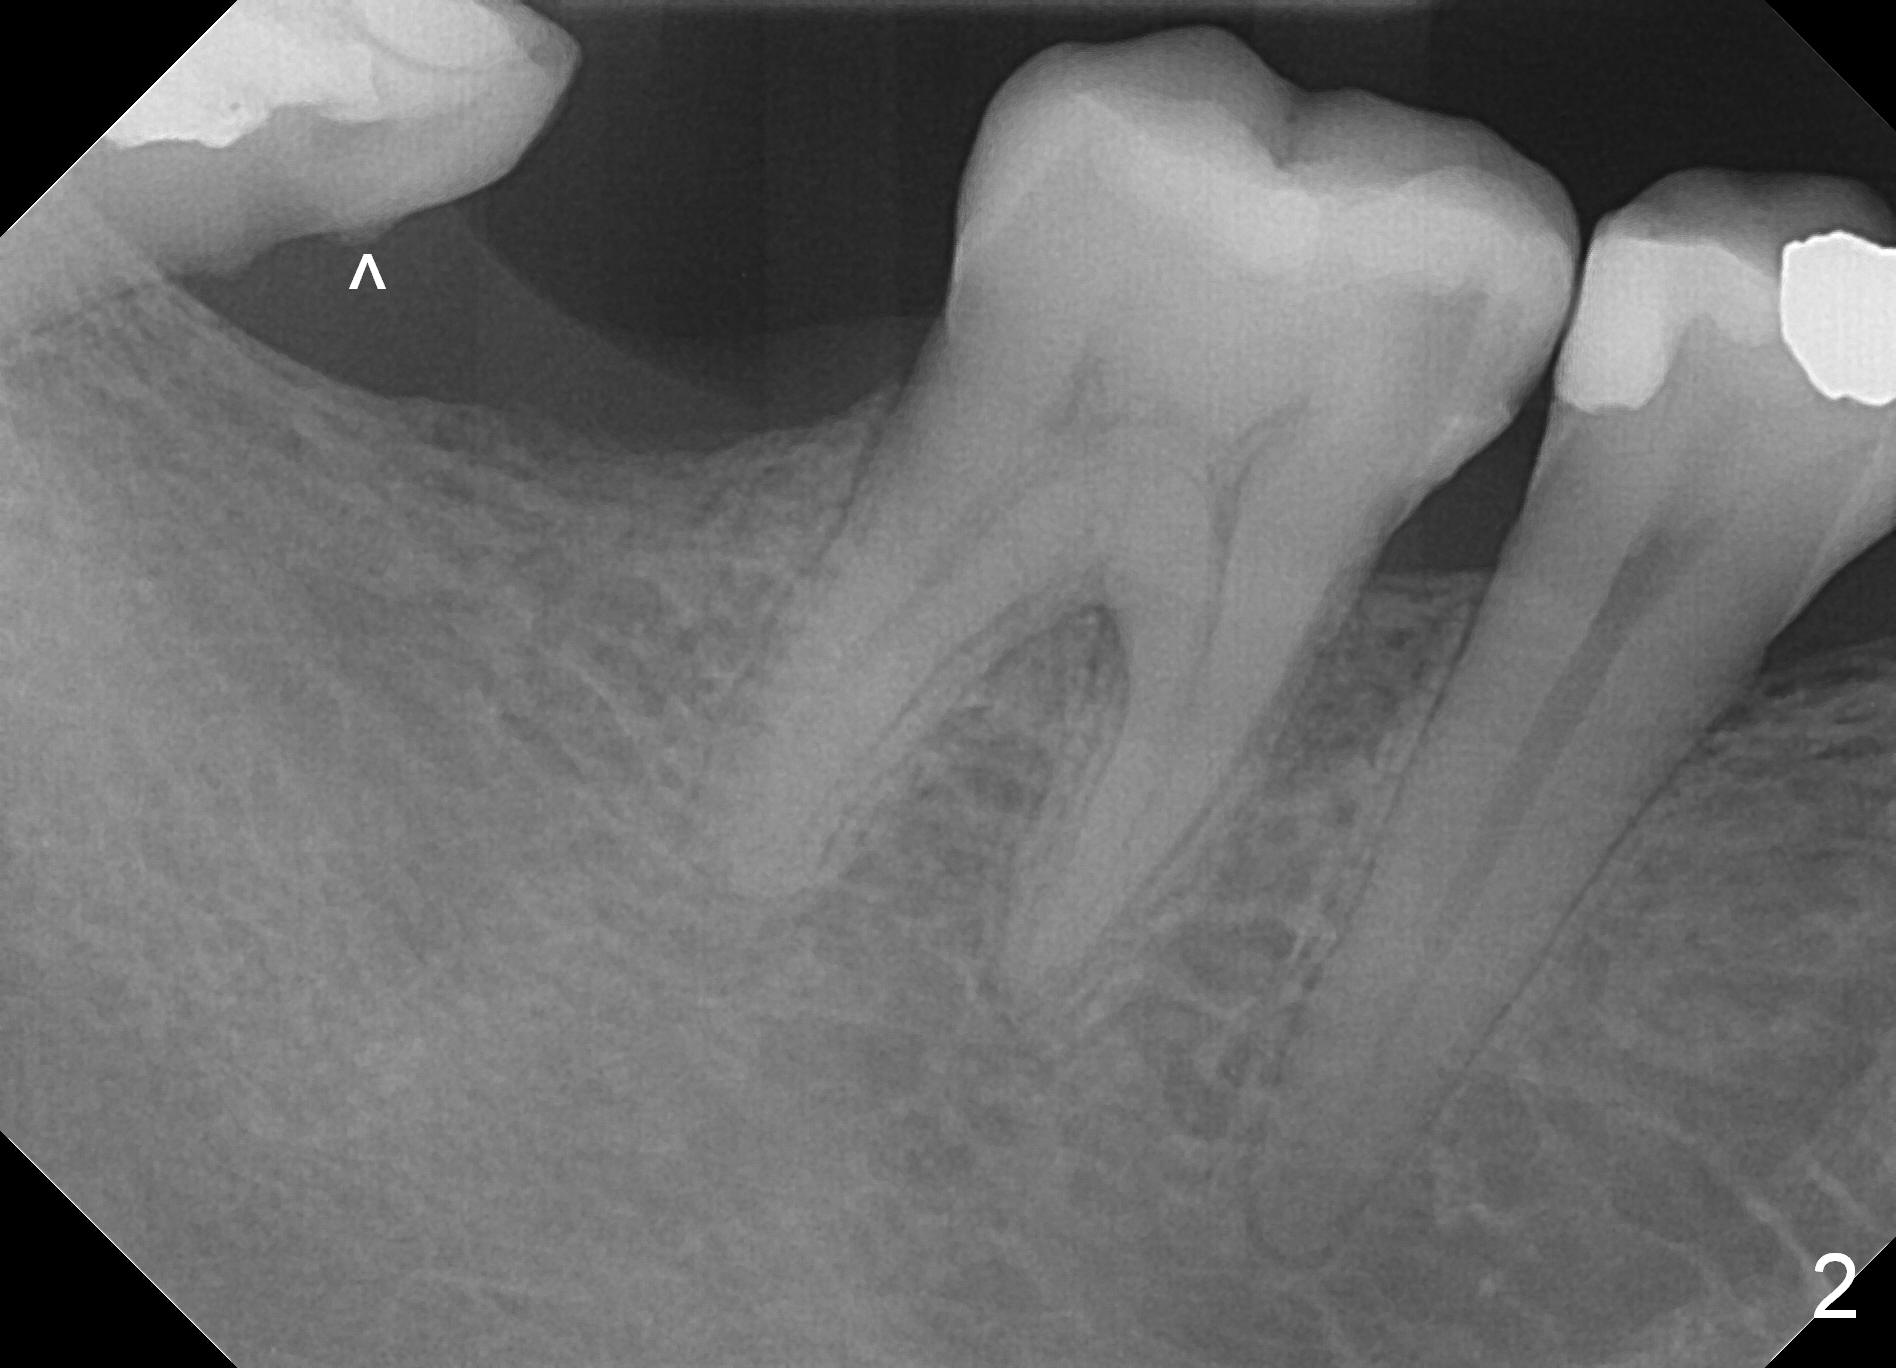

A 39-year-old man presents to office for #19/20 composite redo. After discussion he agrees to restore #31 with implant (Fig.1-3). He worries about bone loss (buccolingually) because of 8-year loss of the tooth. Fortunately the mesiodistal space is less than 8 mm (Fig.3). A 4 mm IBS implant (Titanium V (Bicon as well) stronger (not easily break) than Titatium IV (Tatum, DIO)) should be able to sustain mastication if the tooth #32 is not extracted. After local anesthesia, remove calculus in the mesial surface of #32 (Fig.2 ^). Also prepare for MO composite at #30.